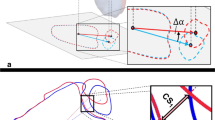

With the lateral fibular bone tunnels unchanged, the fibula samples were moved anteriorly and posteriorly by 1 cm to establish the ant-malreduction and post-malreduction groups, respectively. Then, a 3D-printed guide plate was used to re-fix the specimens, in order to form the malreduction model (ant-malreduction and post-malreduction groups). Afterwards, the same biomechanical tests were performed, and data were collected as the ant-malreduction and post-malreduction groups. Figure 1 presents the experimental protocol, Fig. 2 shows the experimental setup, and Fig. 3 shows the CT scan of three bone tunnels made by template.

The Optotrak Certus motion analysis system (Northern Digital Inc., Ontario, Canada) was applied to capture the motion of the tibia and fibula. Four active optical markers were firmly fixed on the middle of the tibia and fibula, in order to set the base coordinate system. Another two active optical markers were placed on the incisura of the syndesmosis on the fibular side and tibial side, in order to record the initial coordinates of the two bone landmarks. All displacements and relative angles of the syndesmosis during the test were captured in this system. Before the test, all markers were captured at a sampling rate of 100 Hz for 5 s to record the initial relative position between the incisura edge of the syndesmosis in the tibial and fibular side. The whole set of the apparatus and detail were showed in Fig. 2.

For coronal displacement, merely intact and posterior malreduction (P = 0.013), and anatomical and posterior malreduction (P = 0.038) were significantly different (intact vs. anatomical, P = 0.607; intact vs. ant-malreduction, P = 0.179; anatomical vs. ant-malreduction, P = 0.394; post-malreduction vs. ant-malreduction, P = 0.192) (Fig. 2).